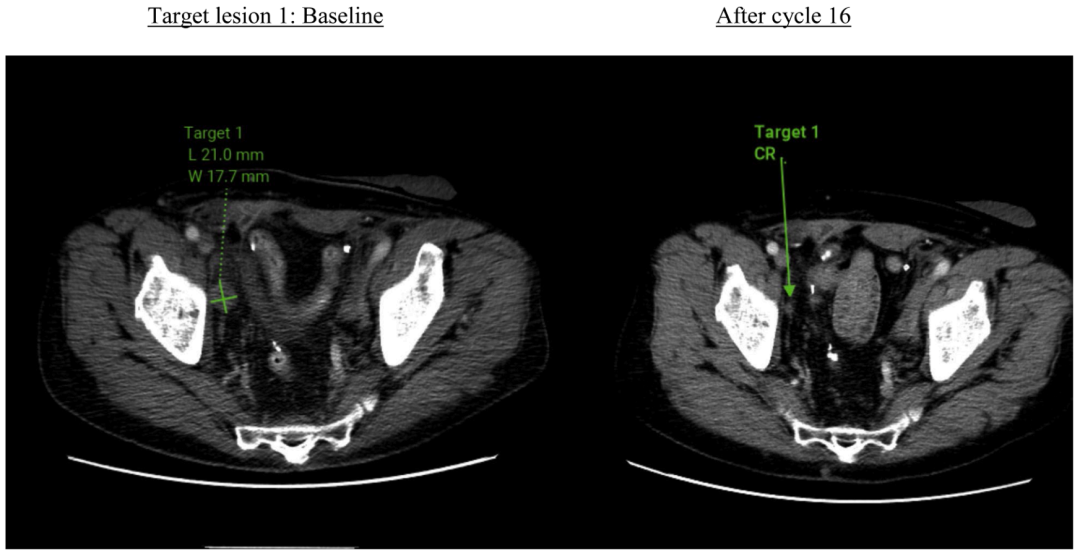

根据RECIST 1.1标准评价,该患者的最佳疗效评价为部分缓解(PR)。影像学数据显示,目标病灶的体积较基线水平缩小了31.7%。

图1 靶病灶退缩情况